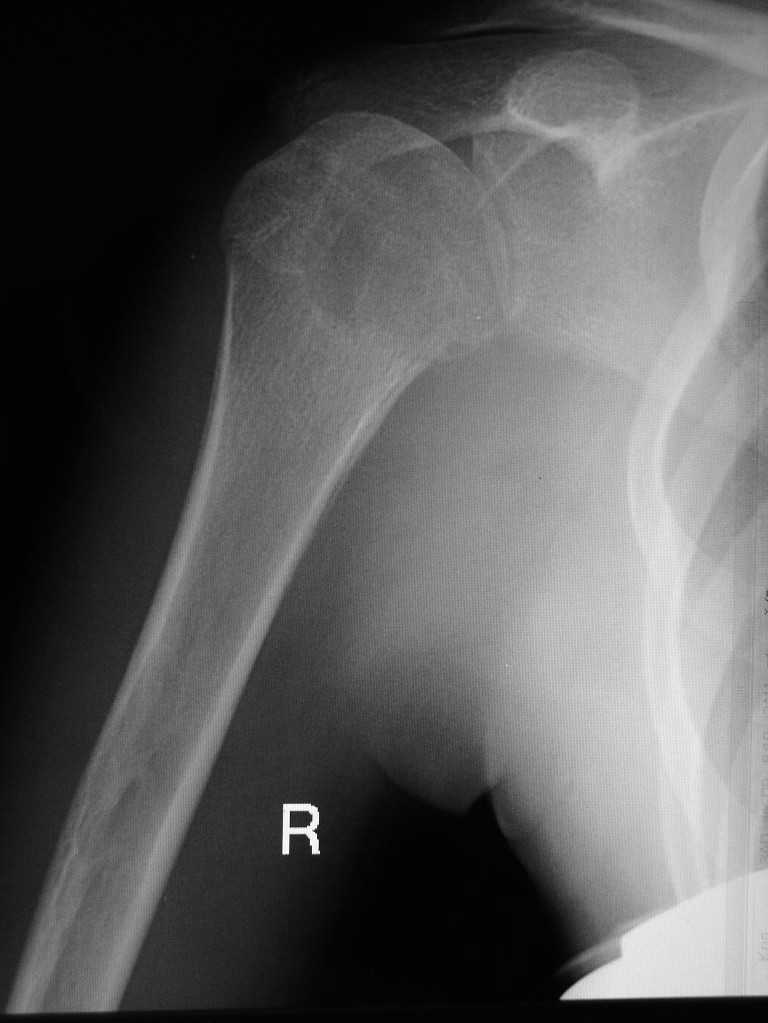

Здравствуйте уважаемые коллеги. Прошу помочь определится с диагнозом. Девушка 16 лет, в течении 10 мес. беспокоят боли в правом плечевом суставе. Последних два месяца возникло резкое ограничение подвижности в суставе. Со слов больной и родителей месяц назад проходила курс лечения у травматолога с диагнозом "периартрит". На момент осмотра плечо отведено до 40 град., активные и пассивные движения резко ограничены, болезненны. Кожные покровы не изменены, пальпация сустава болезненна, общ. ан. крови - норма. Снимки прилагаю. Заранее благодарен за помощь.

Громадный очаг деструкции в головке плечевой кости, резко сужена суставная щель. Для уточнения - вторая проекция, КТ.

У девочки Lytic lesion в головке плеча. Lesion довольно агресивный. Нет четкой границы. Есть периостальная реакция.

очаг деструкции, с достаточно четким контуром, занимающий 75% эпиметафиза плечевой кости, прерывающий кортикальный слой по внутренней поверхности, с периостальной реакцией, у девушки 16 лет - наиболее вероятно, что это гигантоклеточная опухоль с признаками малигнизации.